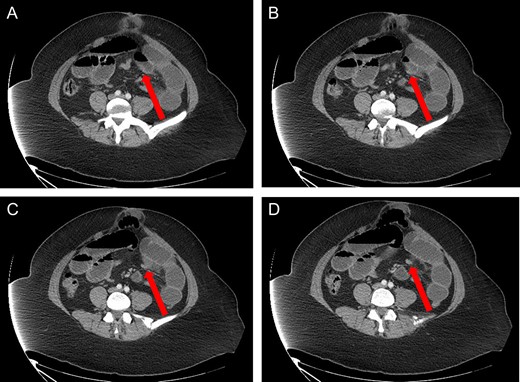

Axial view: (A) and (B) arrows pointing to dilated small bowel from the closed loop obstruction. (C) and (D) arrows pointing to the transition point, where the small bowel is collapsed distally.

A 40-year-old woman presented to the emergency department with abdominal pain for 4 days. She had previously been seen at an outside hospital 3 days earlier, and was diagnosed with biliary colic. Her pain was constant, and was associated with nausea and vomiting. She had a history of a cesarean section, but no other abdominal surgeries. Her vitals were within normal limits: afebrile at 36.9°C, heart rate 71 beats/minute, blood pressure 143/62 mmHg, respiratory rate 18 breaths/minute, and oxygen saturation 97% on room air. On abdominal exam, she was distended, tender, demonstrated voluntary guarding and was positive for peritonitis. Laboratory values were significant for a white blood cell count of 16.1 K/ul, with 80.2% neutrophils, hemoglobin 14.9 g/dl, hematocrit 45.4%, platelets 349 K/ul and lactic acid 0.9 mEq/L; her chemistry was unremarkable. A computed-tomography (CT) scan of the abdomen and pelvis that was obtained prior to surgical consultation demonstrated the proximal two-thirds of small bowel dilated up to 4 cm, with a sharp transition point in the left mid-abdomen, and collapsed small bowel loops near the cecum. The colon was mostly collapsed. A few distended loops bulged into a paraumbilical hernia, which was 6 cm wide and not the cause of obstruction (Figs 1–3).